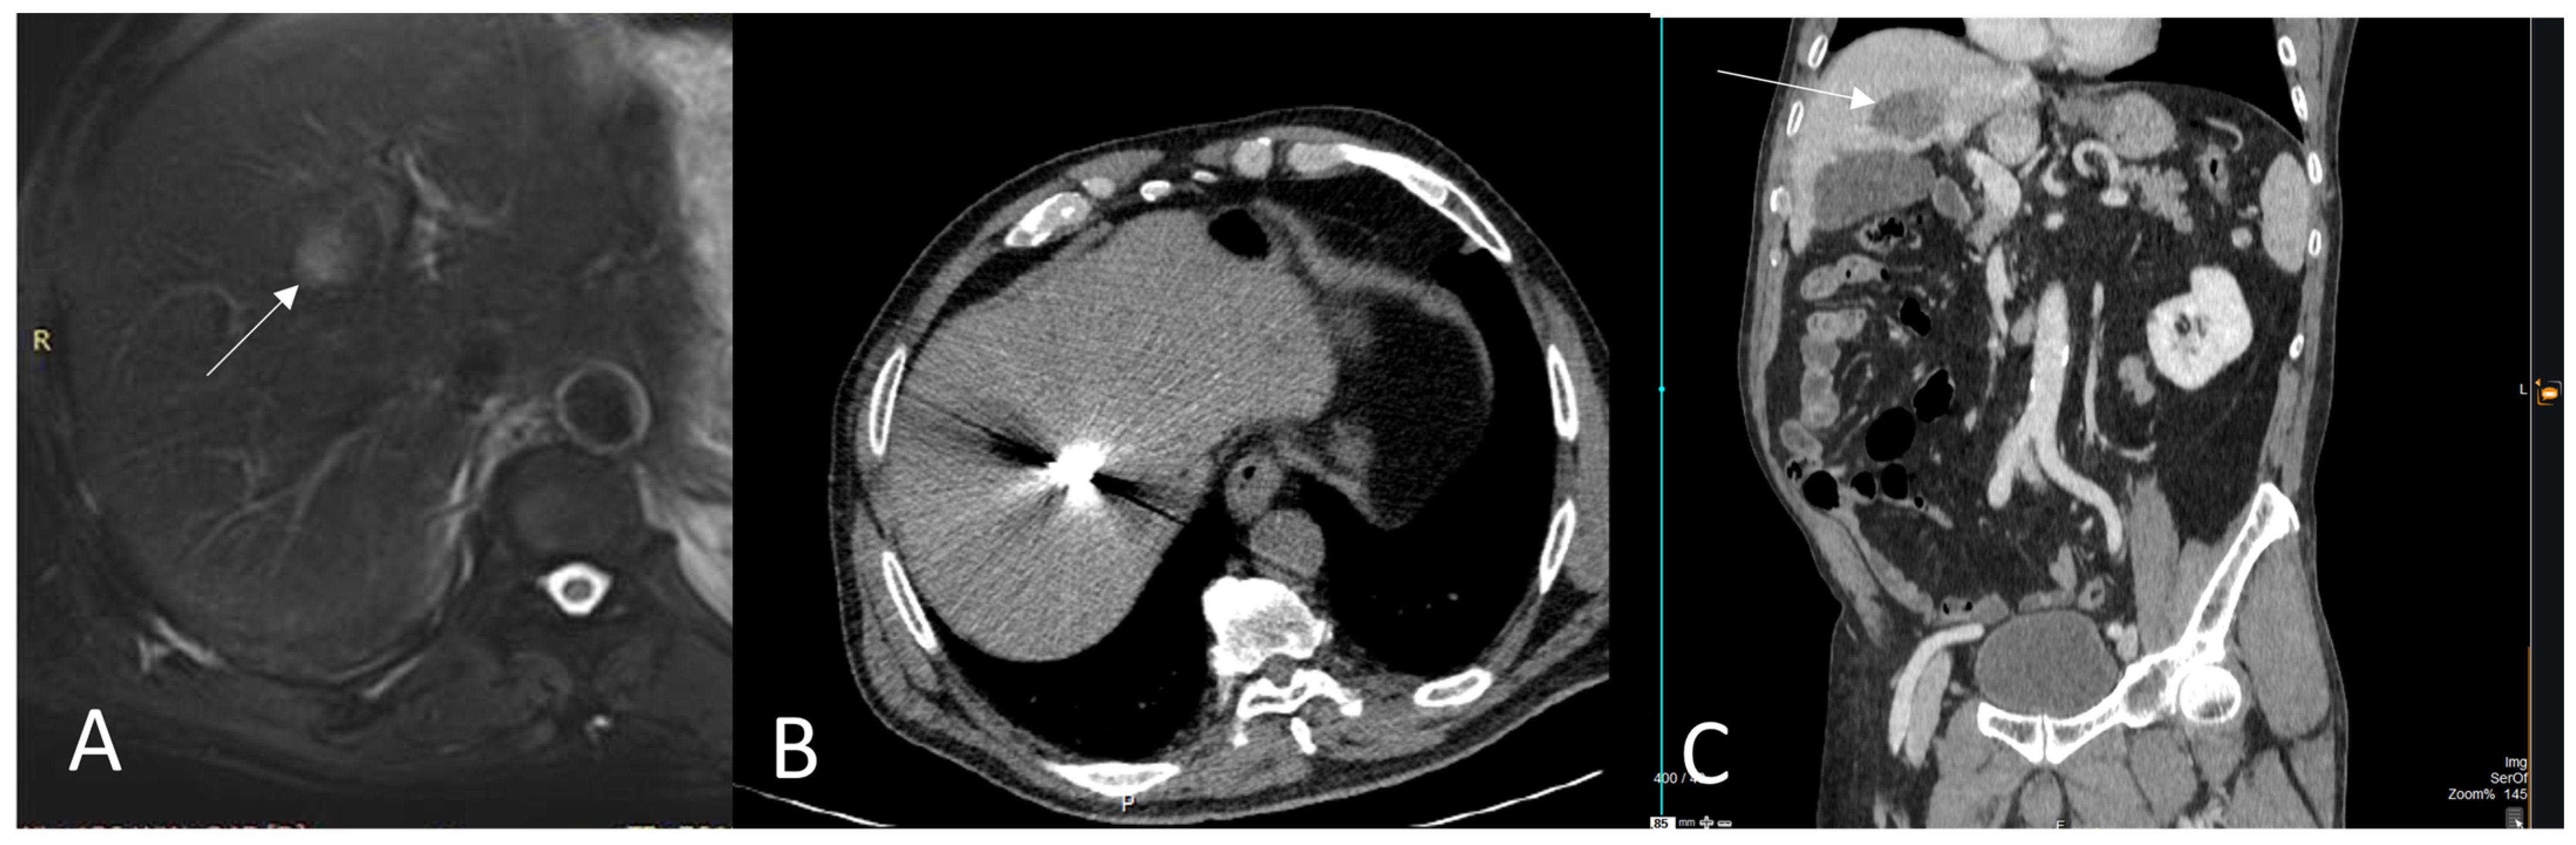

3. Thermal Ablation of Liver Metastasis

| Jones et al. [37] | CT guided RFA | GIST | 13 | - | 21 | 28 months | 2-year overall survival was 77% | 3 patients with sepsis |

| Jung et al. [36] | US guided RFA | GIST | 29 | 1.3 cm | 33.1 | 6% showed local recurrence at 3.2 and 10.5 months | 90.2 months | 1 patient with bleeding at the ablation site & 1 peritoneal seeding near the ablation tract |

| Littrup et al. [38] | CT guided CA | Various | 49 | - | 20 | - | - |